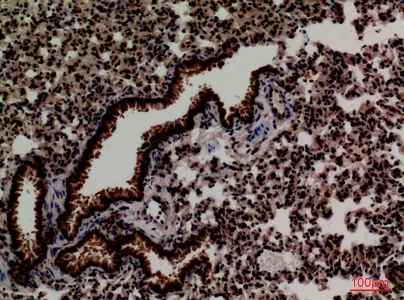

FOXP1 Rabbit Polyclonal Antibody

Cat: APRab11113

Size1:50μl Price1:$118

Size2:100μl Price2:$220

Size3:500μl Price3:$980

Size2:100μl Price2:$220

Size3:500μl Price3:$980